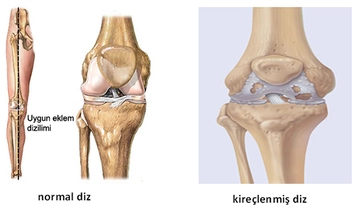

Ayak Bileği Kıkırdak Ameliyatı Nedir Ve Nasıl Yapılır?Ayak bileği, vücudun en önemli eklemlerinden biridir ve günlük hareketlerimizde büyük bir rol oynamaktadır. Ancak, çeşitli travmalar veya dejeneratif hastalıklar sonucunda ayak bileği kıkırdaklarında hasar meydana gelebilir. Bu durum, ağrı, şişlik ve hareket kısıtlılığına neden olabilir. Ayak bileği kıkırdak ameliyatı, bu tür sorunların tedavisinde uygulanan cerrahi bir yöntemdir. Ayak Bileği Kıkırdak Hasarının NedenleriAyak bileği kıkırdak hasarının başlıca nedenleri arasında şunlar yer almaktadır:

Ameliyat Öncesi DeğerlendirmeAyak bileği kıkırdak ameliyatı, kapsamlı bir değerlendirme sürecini gerektirir. Bu aşamada doktor, hastanın tıbbi geçmişini gözden geçirir ve fizik muayene yapar. Ayrıca, aşağıdaki görüntüleme yöntemleri kullanılabilir: